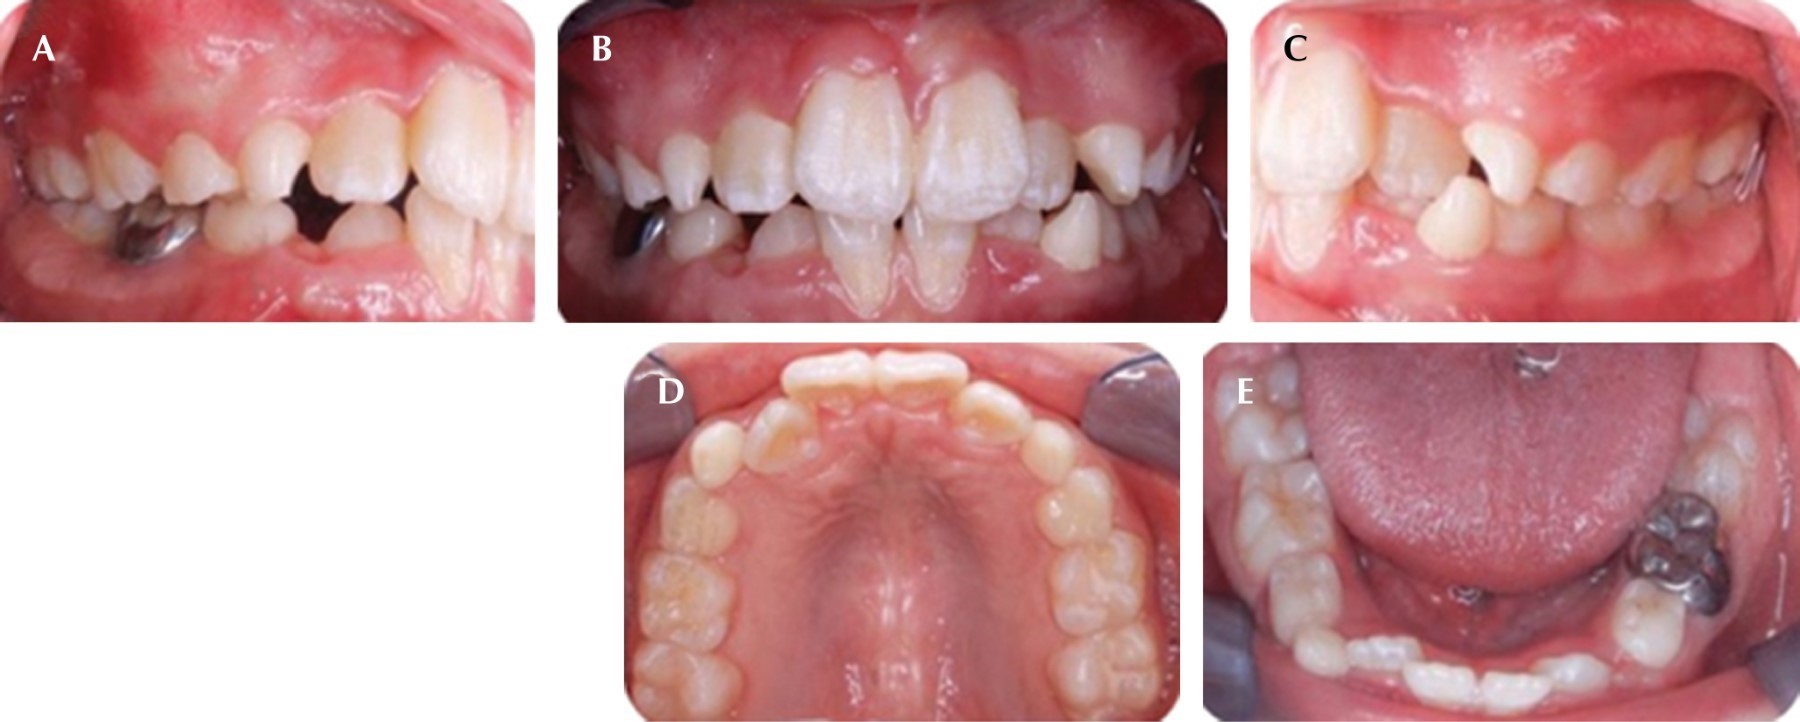

El estado actual del paciente es estable, anteriormente ya había sido atendida odontológicamente y su experiencia fue negativa. De acuerdo con la Academia Americana de Anestesiología13 se clasificó como ASA II (paciente con enfermedad sistémica leve o compensada). En la exploración clínica extraoral se observó cara redonda, tercio medio aumentado, ligera asimetría facial, perfil convexo y retrognatismo mandibular (Figura 2). La paciente tiene una conducta no cooperadora y se clasifica en una escala de Frankl 2,14 por lo que la exploración oral inicial se realizó fuera del sillón dental. Las características clínicas intraorales observadas fueron: boca simétrica con mal posición dentaria por falta de espacio, retraso en la erupción dentaria, microdoncia, micrognatia, línea media desviada, presencia de dentición mixta, arcadas de forma cuadrada, mucosas hidratadas, clase I molar derecha e izquierda y apiñamiento dental (Figura 3). Se solicitó radiografía lateral de cráneo y el análisis vertebral indicó un estadio CS3, los bordes inferiores de C2 y C3 mostraron concavidades y C4 superficies planas (Figura 4A). En la radiografía panorámica se observó agenesia de órgano dentario 42 (Figura 4B).

Figura 3